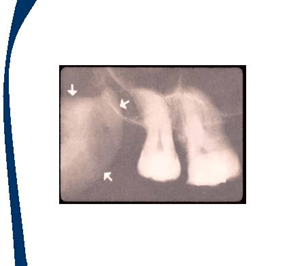

En las imagenes aparecen flechas que representan la localización de los landmarks o puntos de referencia

Puntos de referencia de dientes posteriores maxilares

Seno maxilar

Hueso cigomatico

Tuberosidad maxilar

Proceso hamular

Muesca hamular

Proceso coronoideo de la mandibula.